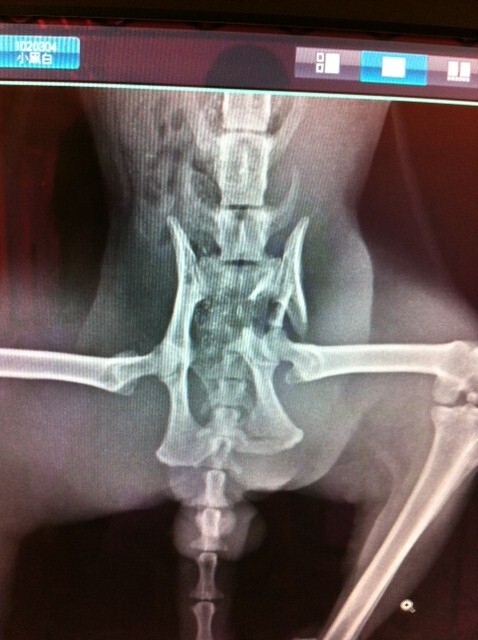

隔日送到極光動物醫院, 做了檢驗以及X光, 估計是被車撞, 檢驗的部份, 下巴脫臼, X光片顯示骨盆骨折, 骨盆腔變小, 直腸被擠到一邊, 日後恐影響無法排便, 醫師判斷自行復原不易, 需要做手術, 血檢發現貓愛滋及貓瘟, 考量到日後小黑白回到街上的生存以及手術有時間上的考量, 最後決定幫他動骨盆手術

下巴的部份醫師已先接回